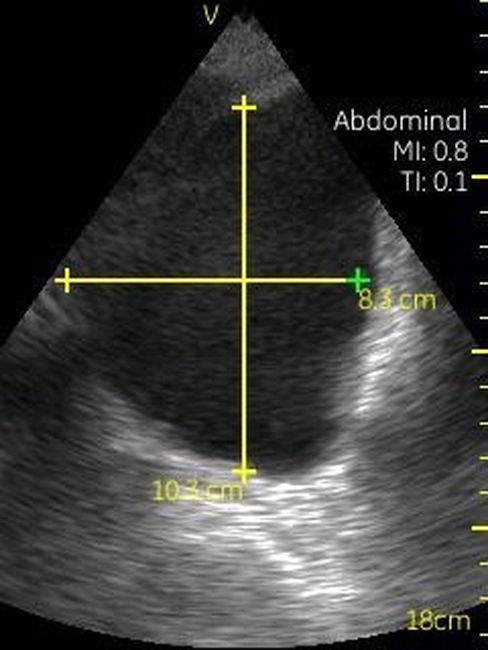

Визуализация Vscan:

· Черно-белый режим для визуализации анатомических структур в реальном времени.

· Наложение кровотока с цветовой кодировкой в реальном времени.

· Поле зрения в черно-белом режиме: до 75 градусов с максимальной глубиной 25 см.

· Сектор цветного режима показывает кровоток с углом обзора 30 градусов

· Широкополосный фазированный датчик с частотой от 1,7 до 3,8 МГц.